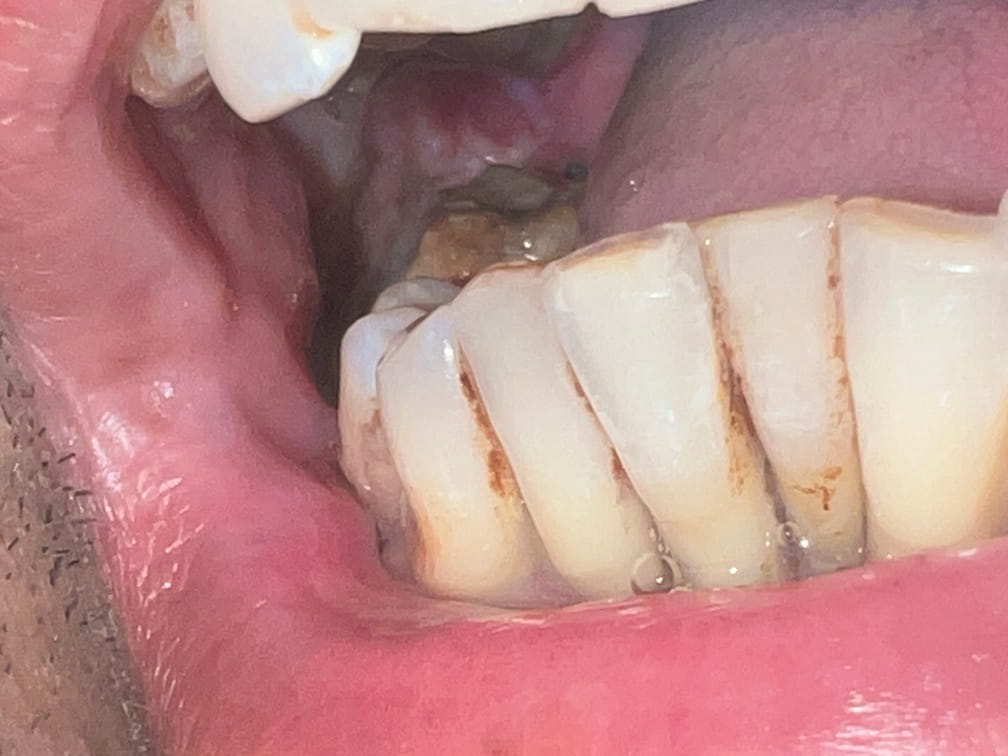

42 years old male suffering from right lower Gingivo buccal growth involving mandible .CT scan shows level 1 ,2 lymphadenopathy .Right modified neck dissection with right hemimandibulectomy with right pectoralis flape done.

21-04-2026